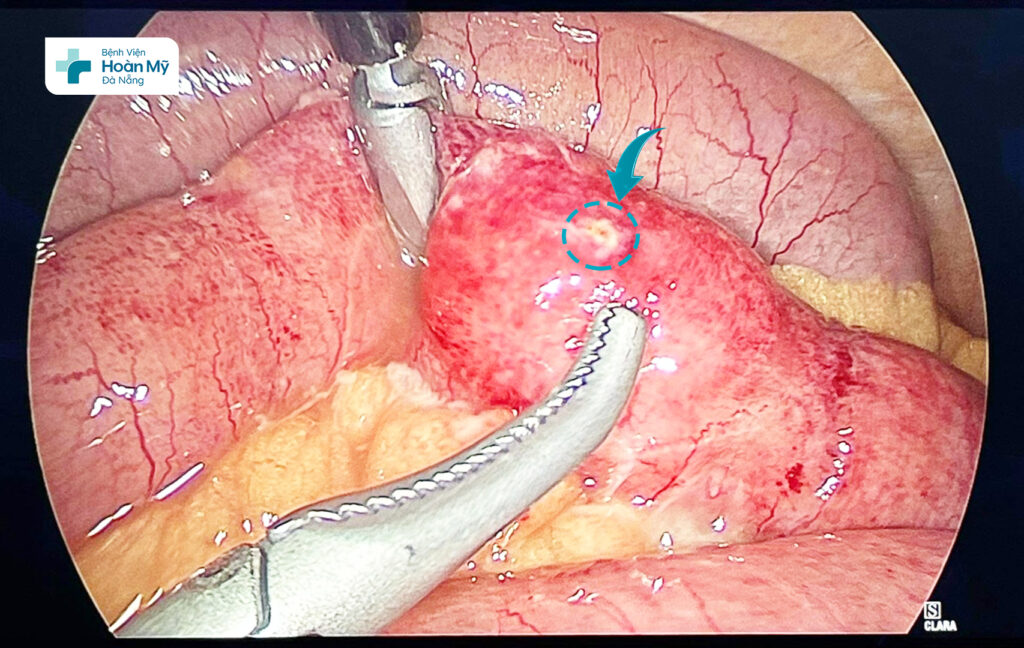

Trưa 21/7, Khoa Cấp cứu – Bệnh viện Hoàn Mỹ Đà Nẵng tiếp nhận một trường hợp vào viện vì đau bụng nhiều vùng bụng quanh và dưới rốn, khởi phát từ sáng và ngày càng tăng, cơn đau liên tục, không có cơn trội. Tại Khoa Cấp cứu, người bệnh được thăm khám, siêu âm bụng, chụp cắt lớp vi tính ổ bụng và làm một số xét nghiệm máu để chẩn đoán bệnh. Kết quả phát hiện một dị vật bất thường (nghi là mảnh xương) đâm xuyên thành ruột non. Xác định nguy cơ dị vật đâm thủng ruột non có thể gây ra những biến chứng phức tạp, người bệnh được các bác sĩ hội chẩn và chỉ định phẫu thuật nội soi cấp cứu lấy dị vật. Trong quá trình phẫu thuật, các bác sĩ phát hiện dị vật là mảnh xương gà đâm thủng ruột non của người bệnh, gây nên tình trạng viêm phúc mạc. Sau khoảng gần 01 giờ phẫu thuật nội soi can thiệp, ekip đã gặp thành công dị vật đường tiêu hóa cho người bệnh một cách an toàn.

Lỗ thủng ở ruột non do dị vật gây ra

ThS.BSNT Phạm Trọng Khôi – đại diện ekip phẫu thuật cho biết: “Thủng ruột non nói riêng hay bất kỳ lỗ thủng nào tại đường tiêu hoá nói chung đều gây chảy dịch tiêu hoá vào ổ bụng, gây nên tình trạng viêm phúc mạc, có thể dẫn đến nhiễm trùng huyết, thậm chí là nguy hiểm đến tính mạng. Ở người bệnh này, nhờ đến bệnh viện sớm và được phẫu thuật cấp cứu kịp thời nên chưa dẫn đến các biến chứng nặng, vì vậy quá trình hồi phục sau mổ diễn ra một cách thuận lợi”.